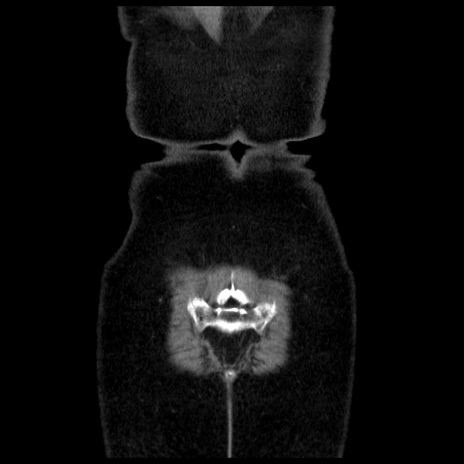

症例13(冠状断像)

【症例】70歳代女性

【主訴】腹痛、嘔吐

【現病歴】15時間程前(昨晩)より腹痛あり。今朝になっても症状の改善なく、嘔吐あり。腹痛も増悪あり、救急外来受診。

【既往歴】子宮癌全摘術後

【身体所見】意識清明、BP 121/72mmHg、P 74bpm、SpO2 100%(RA)、腹部:平坦・軟、腸雑音ほぼ聴取せず。下腹部・心窩部・臍左上に圧痛あり。反跳痛なし。

【データ】WBC 10600、CRP 0.15